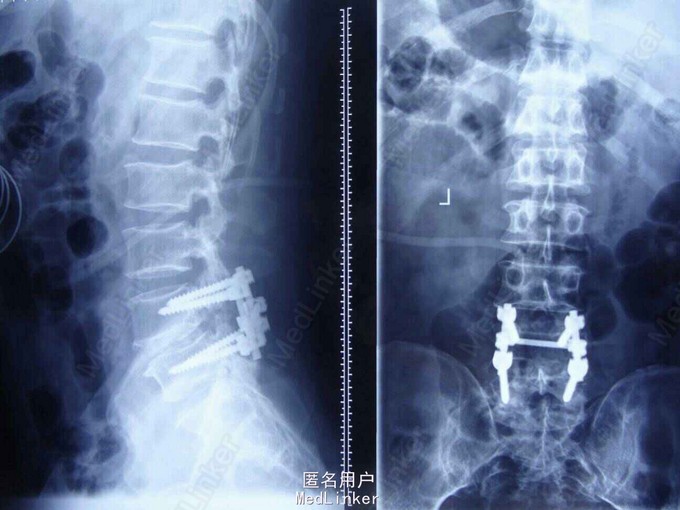

诊断: 腰4椎体滑脱(I度)、腰椎管狭窄(L4-5) 治疗原则: 择期手术治疗。于全麻下行腰椎后路切开复位植骨融合内固定术,术后给予抗炎、营养及对症治疗。

1.腰围固定,全休三个月,避免剧烈活动; 2.定期门诊复查; 3.病情变化随时诊治。